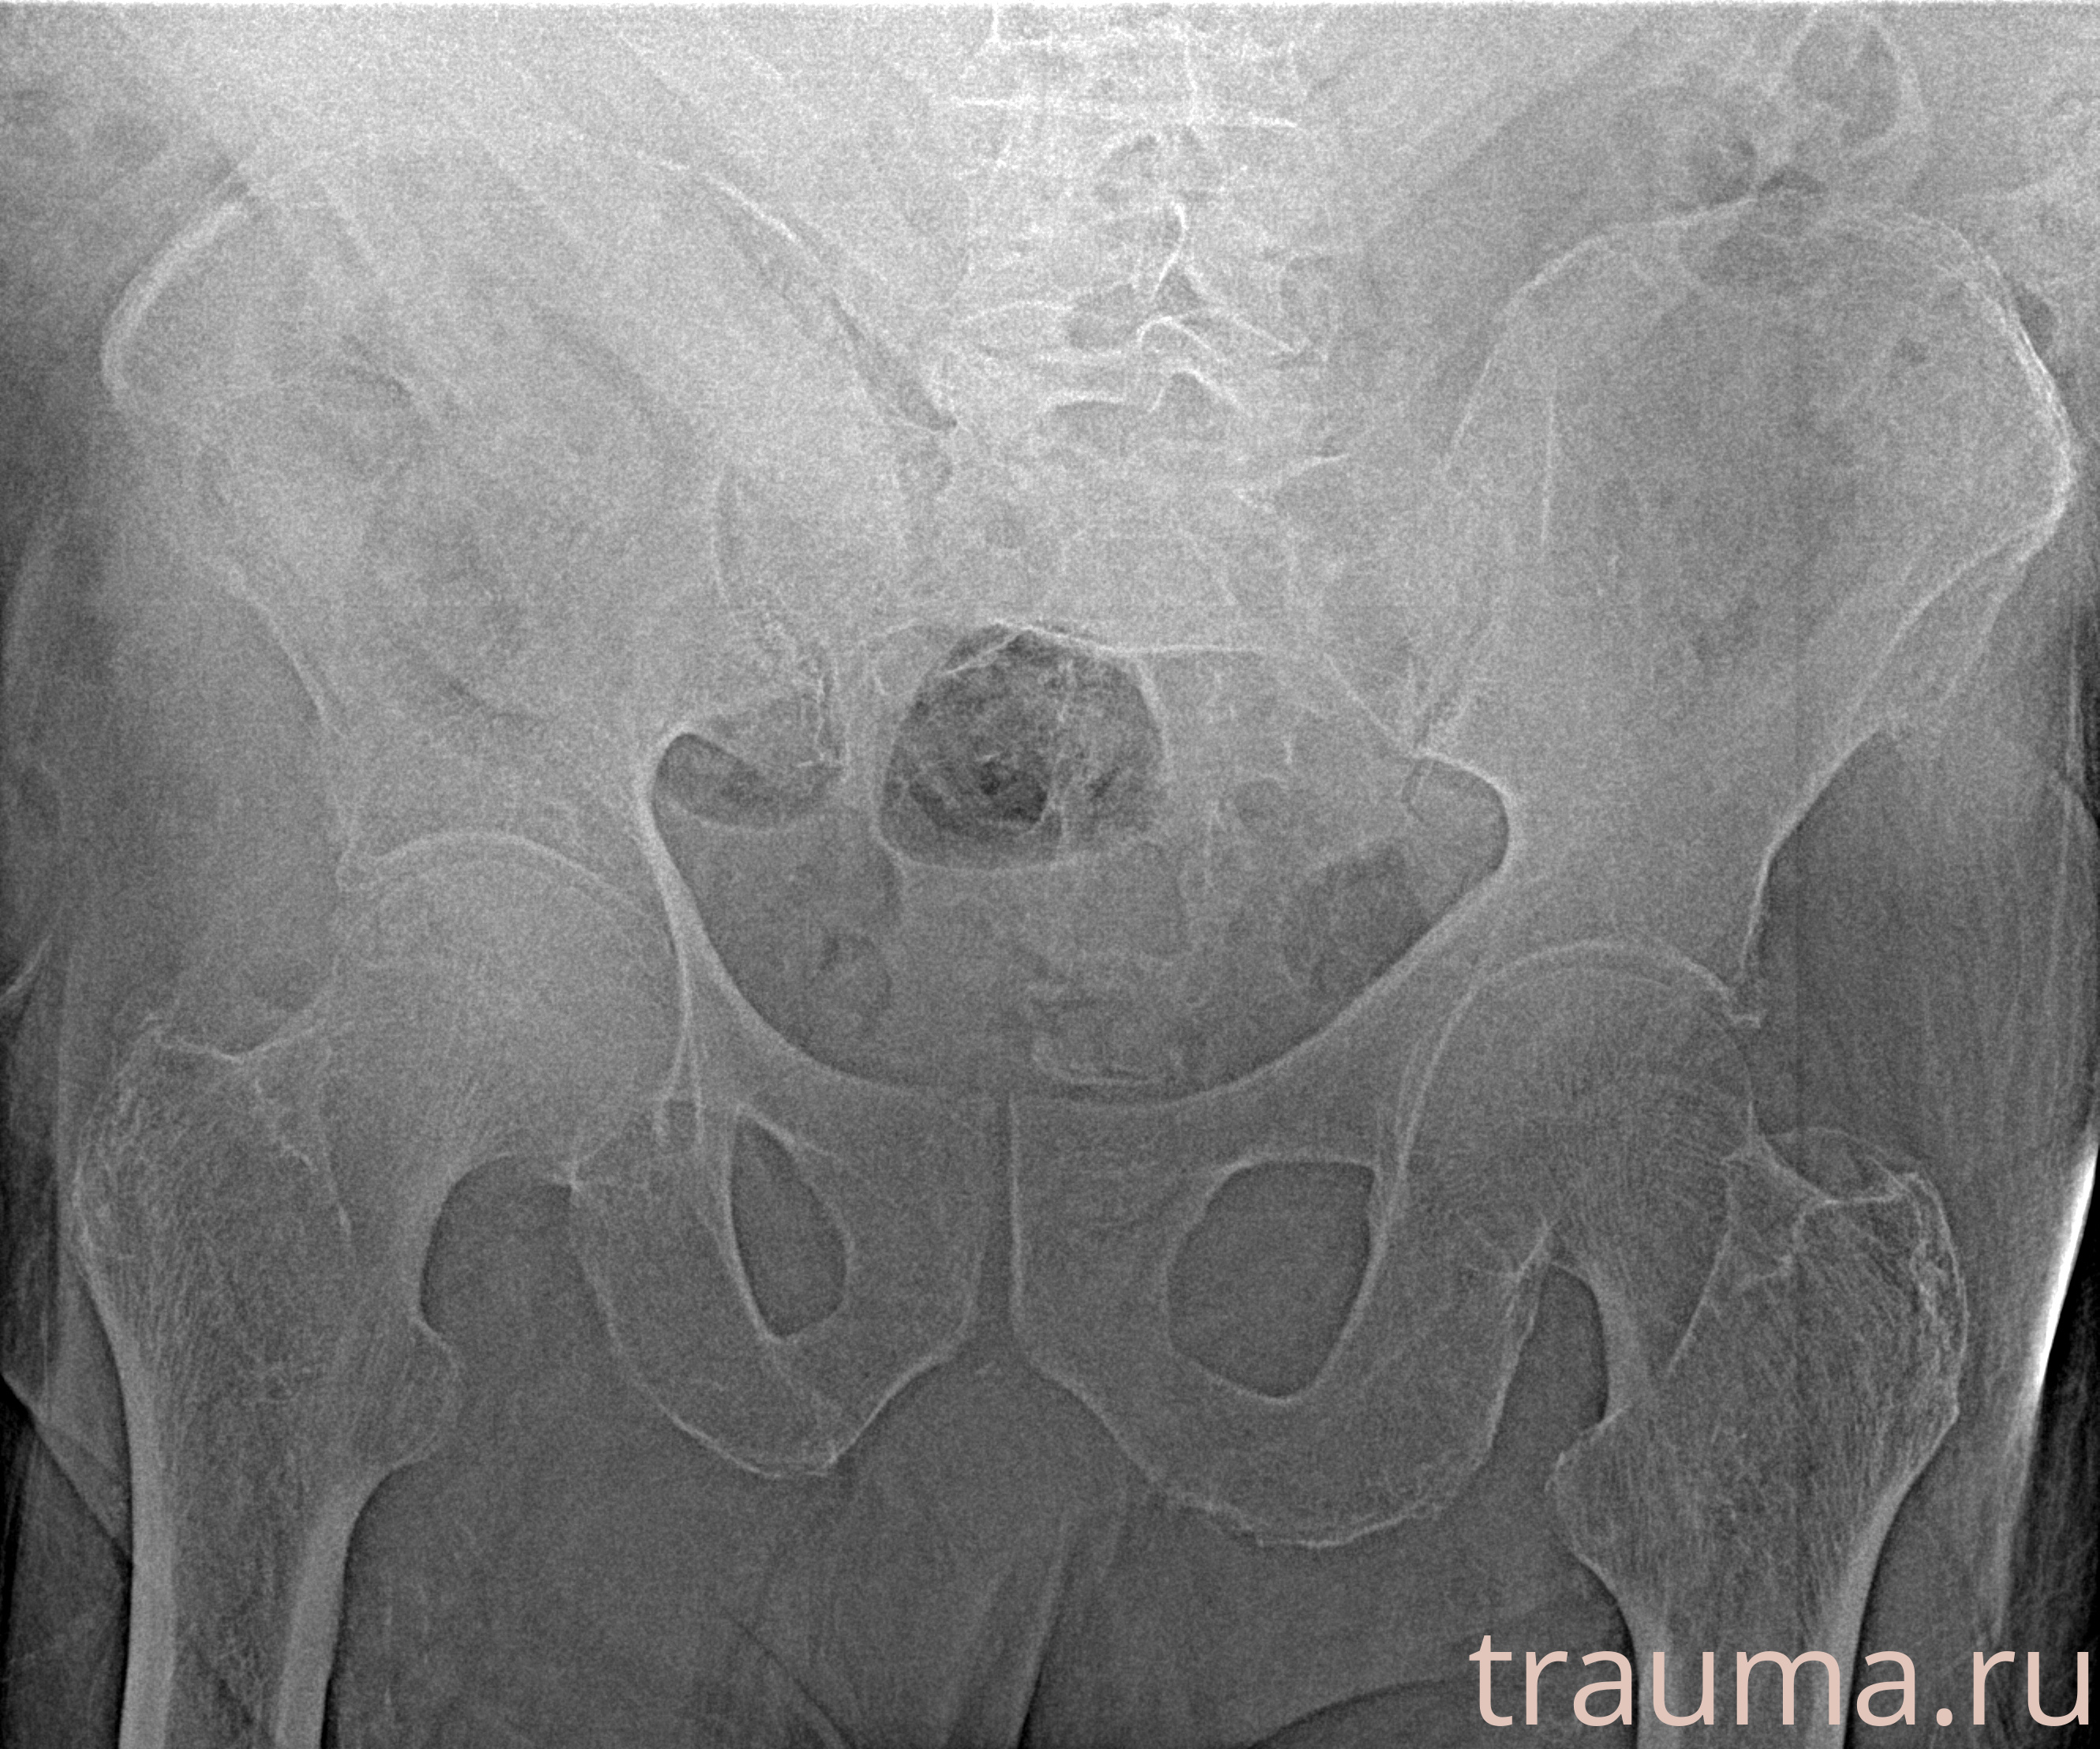

Рентгенограммы

Рентген на дому: по вашему адресу приезжает врач-рентгенолог, травматолог-ортопед с мобильным рентгеновским аппаратом, проводит диагностику травмы или заболевания, делает необходимые рентгенограммы, дает рекомендации по дальнейшему лечению. Получить качественные снимки в домашних условиях возможно благодаря уникальной методике, разработанной МосРентген Центром для института  Склифосовского